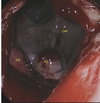

FIGURE 13 B, The corresponding right Plica vocalis at 30-50 days postsurgery on endoscopy. The Plica vocalis abscess clearly seen as a yellowish-greenish

mass covered in mucoid material (white arrow). Right to the left of the image